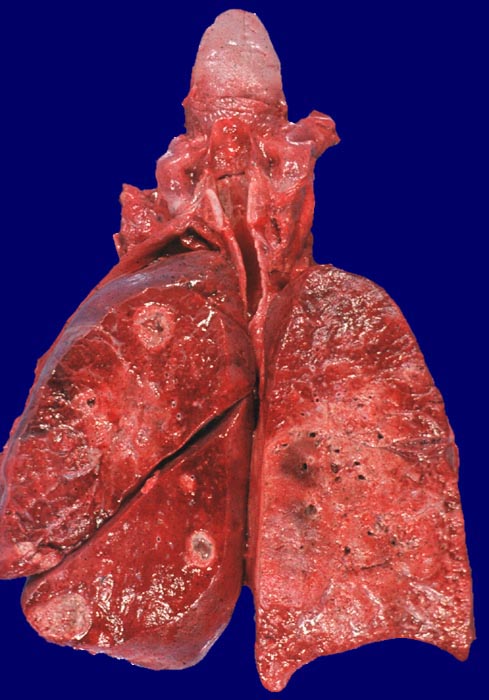

Nekrosen und Abszesse bei Wegener Granulomatose

Lunge

Die Lungen zeigen ein verfestigtes Parenchym mit mehreren runden zentral eingeschmolzenen Abszessen in den Lappen der linken Lunge.